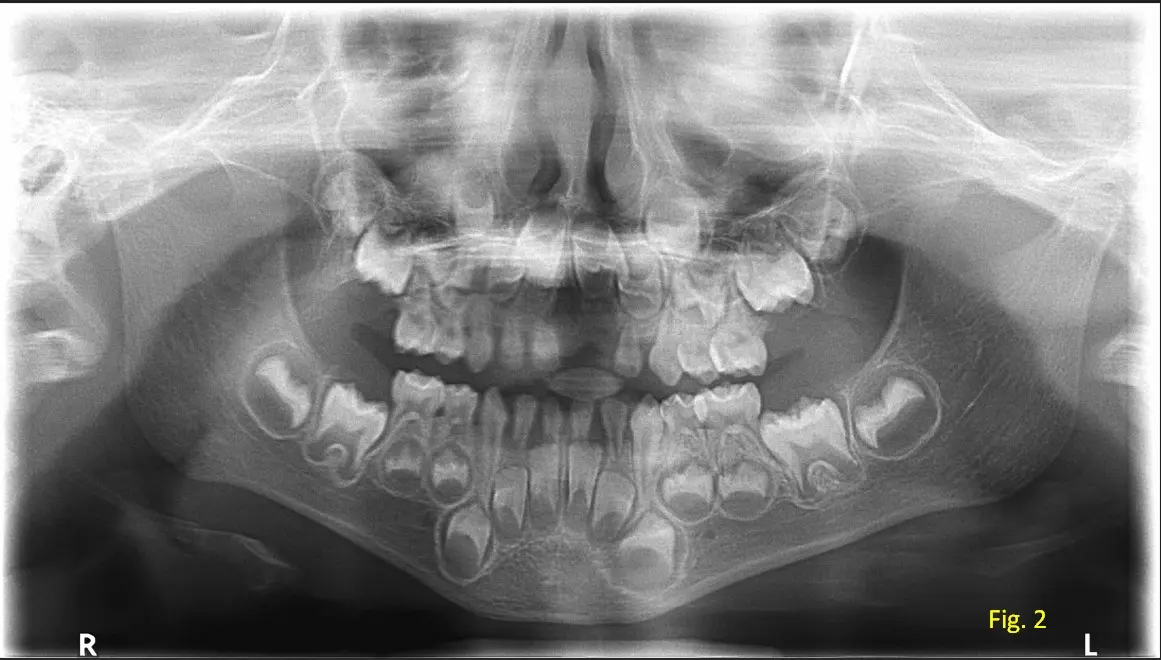

Al observar la radiografía panorámica, (ver figura 2) la odontóloga comenta que los dientes temporales, del paciente ya se encuentran próximos al recambio, dado que los gérmenes de los dientes permanentes están en proceso activo de erupción. Además, se evidencia espacios suficientes en las arcadas dentarias para permitir la erupción adecuada y alineada de los dientes permanentes definitivos, sin signos de apiñamiento o interferencias óseas.

La radiografía panorámica, aun en pacientes pediátricos, resulta una herramienta fundamental para el diagnostico post-trauma, ya que brinda una visión amplia y no invasiva del desarrollo dentario y estructuras adyacentes.

Su uso oportuno permitió un abordaje adecuado del caso y una planificación a futuro para el seguimiento del desarrollo dental del niño.